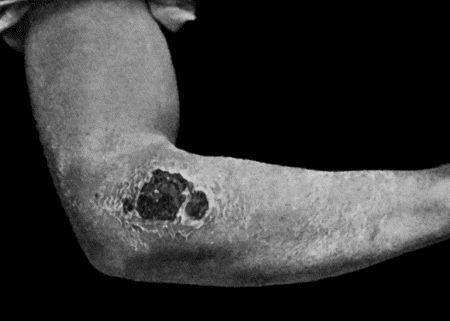

Fig. 3.—Streptococci in Pus from an acute abscess in subcutaneous tissue. × 1000 diam. Gram's stain.

Streptococcus Pyogenes.—This organism also varies greatly in its virulence; in some instances—for example in erysipelas—it causes a sharp attack of acute spreading inflammation, which soon subsides without showing any tendency to end in suppuration; under other conditions it gives rise to a generalised infection which rapidly proves fatal. The streptococcus has less capacity of liquefying the tissues than the staphylococcus, so that pus formation takes place more slowly. At the same time its products are very potent in destroying the tissues in their vicinity, and so interfering with the exudation of leucocytes which would otherwise exercise their protective influence. Streptococci invade the lymph spaces, and are associated with acute spreading conditions such as phlegmonous or erysipelatous inflammations and suppurations, lymphangitis and suppuration in lymph glands, and inflammation of serous and synovial membranes, also with a form of pneumonia which is prone to follow on severe operations in the mouth and throat. Streptococci are also concerned in the production of spreading gangrene and pyæmia.

Division takes place in one axis, so that chains of varying length are formed (Fig. 3). It is less easily cultivated by artificial media than the staphylococcus; it forms a whitish growth.